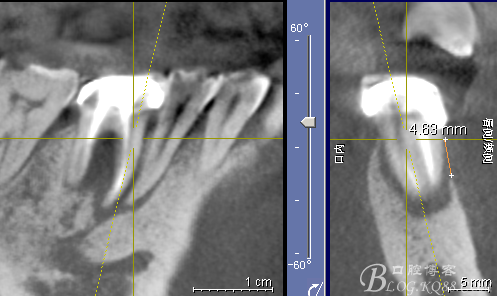

CT可見根管內有白色顯影物和根周較大暗影

懷疑牙根微裂,

所以建議患者手術探查

3月后復查見C5根尖有吸收

C6骨吸收明顯